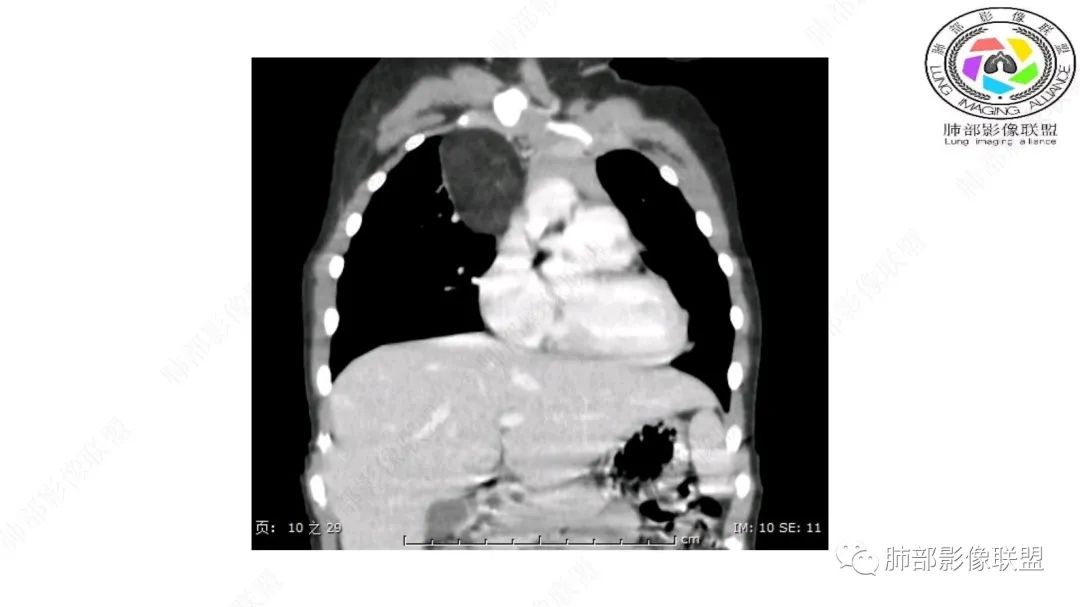

右上纵隔混杂密度肿块,边缘光整,与纵隔分界清,其内多发脂肪密度,增强无明显强化,其内血管穿行,考虑纵隔脂肪母细胞瘤,鉴别畸胎瘤,脂肪肉瘤。

右纵隔团状,密度不均,脂肪密度为主,内可见腺体样组织,类似乳腺,病灶边缘有分叶,与胸腺关系密切,增强后血管穿行。考虑胸腺脂肪瘤(不典型垂乳征),鉴别畸胎瘤。

三岁小儿,右侧纵隔巨大脂肪密度肿块,肺动脉穿行其中,密度欠均匀,未见明确实性成分,纵隔脂肪母细胞瘤,冬眠瘤鉴别纵隔脂肪增多症(多弥漫对称)。

患儿3岁 咳嗽检查发现纵隔占位。右肺上叶受压表现,占位以脂肪组织密度为主,似见分隔,首先考虑为脂肪母细胞瘤,鉴别脂肪瘤,畸胎瘤。

幼儿,右上纵隔团块状脂肪密度影,边缘清晰,内可见血管及支气管穿行,考虑脂肪瘤,鉴别畸胎瘤。

幼儿,右上纵膈团块,脂肪密度,内见分隔,增强病灶内见血管穿行,结合患者年龄,考虑脂肪母细胞瘤,鉴别脂肪瘤。

纵隔畸胎瘤,右前上纵隔团状脂肪密度?粘液样密度为主病变,病灶软边缘有分叶,内可见分隔,增强后血管穿行。3岁。考虑纵隔脂肪母细胞瘤,鉴别畸胎瘤。

病灶属于交界区,主体位于肺内,占位效应明显,前方突入胸壁,胸腺受压变形,胸膜显示欠清楚;病灶包绕上叶肺动脉;似乎有体动脉供血。符合肺内的点:包绕上叶肺动脉分支;符合纵隔的点:前方似乎突入胸壁,与胸腺关系比较密切,但是与上腔静脉的关系提示病灶不支持纵隔来源,前纵隔的常规会将上腔静脉受压后移、外移,这是不符合的。

手术记录:见右肺上叶肿物,肿物与右肺上叶关系密切。与纵隔无粘连,逐步分离肿物,见肿物大小约6cm*5cm,边界清楚,于右肺上叶粘连,边界清楚,肿物包绕右肺上叶血管及支气管。超声刀逐步游离肿物,完整切除肿物,右肺上叶肺组织无破溃,表面无出血。

2.肺动脉穿行也许是肺内来源最重要支持点!